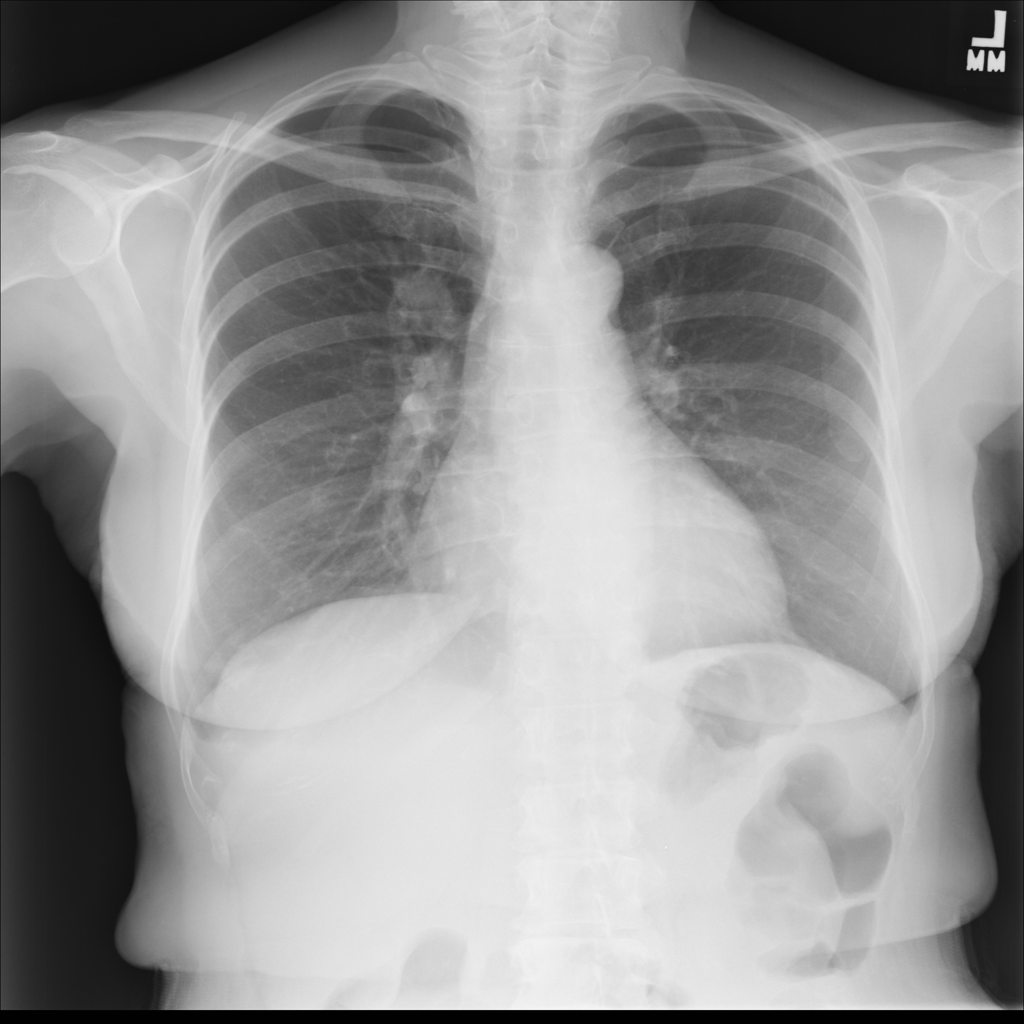

Nodule

A nodule is a small rounded opacity in the lung or chest field. It is a descriptive imaging finding that can be benign or more concerning depending on size, appearance, and context.

Showing up to 90 reference images for Nodule.

PAT-50E5 · IMG-000Nodule

PAT-50E5 · IMG-000

PA